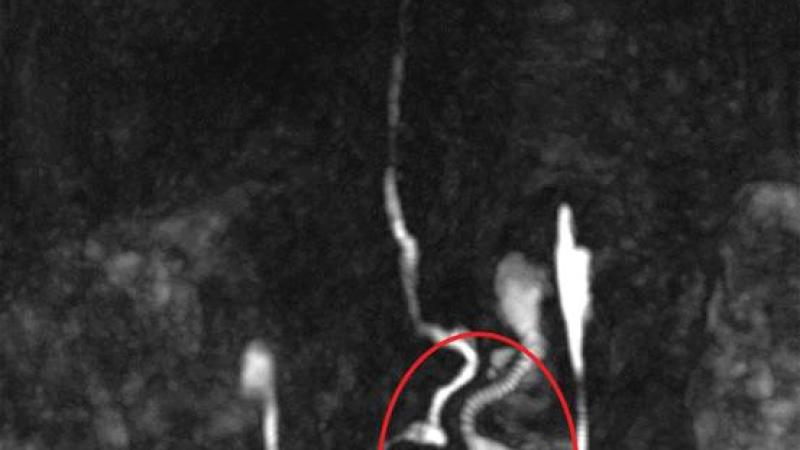

وكانت آلام المرأة مصحوبة بمشاكل حادة في الدورة الدموية، ما جعل من الصعب عليها المشي مسافة 100 متر في المرة الواحدة، مع زيادة الأعراض، تم إجراء تصوير الأوعية اللمفاوية بالرنين المغناطيسي الديناميكي، ما سمح برؤية القنوات والغدد اللمفاوية.

وأظهر تصوير كيسياً للأوعية اللمفاوية في الحوض الأيسر بحجم الكمثرى تقريباً، حيث يتراكم السائل اللمفاوي بشكل متكرر، وأدى ذلك إلى ألم شديد وربما تسبب في مشاكل في الدورة الدموية من خلال التأثير في الجهاز العصبي اللاإرادي وكذلك العمود الفقري.